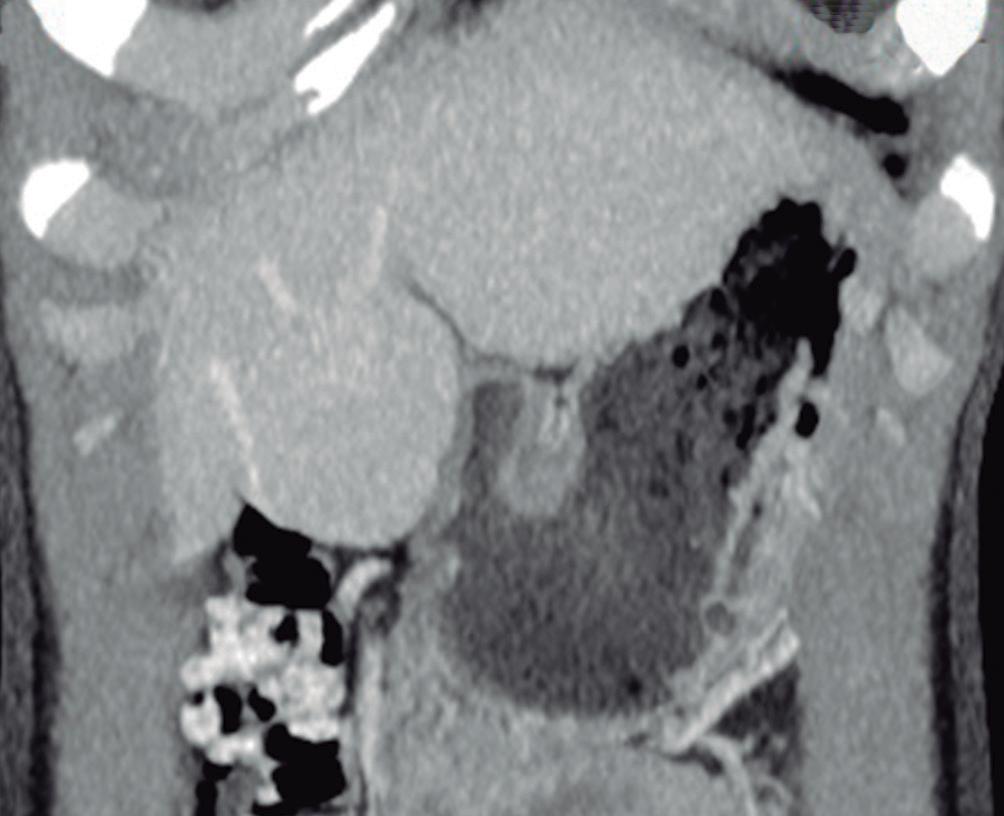

La HNF se manifiesta como uno o más nódulos (múltiple en aproximadamente 20%) de bordes netos y contornos lobulados. En la TCMC tiene densidad similar o apenas menor a la del parénquima adyacente. Si la cicatriz es visible (60%) en la TC es hipodensa. (Figura 3) En la RM su señal es isointensa o apenas hipo o hiperintensa en T1 e isointensa o un tanto hiperintensa en T2. (Figura 4) La cicatriz es hiperintensa en T2 (visible 80% en la RM), característica clave para diferen-

ciarla del hepatocarcinoma fibrolamelar (cuya cicatriz es hipointensa en T2 por fibrosis o por calcificación). Por otra parte, en algunos casos la diferenciación puede ser difícil ya que ambas son lesiones que ocurren en pacientes jóvenes con hígado sano y presentan similar aspecto y comportamiento poscontraste. Típicamente, la lesión realza intensamente en la fase arterial en forma homogénea y su densidad (o intensidad de señal en la RM) disminuye en fases sucesivas pero suele persistir levemente reforzada con respecto al hígado.4, 5 Los hepatocitos que forman la HNF son positivos para las proteínas transportadoras, característica que, sumada a la presencia de conductos biliares, explican el refuerzo de estas lesiones en la fase hepatobiliar en la RM con empleo de contraste hepatoespecífico. Esto permite establecer el diagnostico con un alto grado de certeza y alejar (sin descartar absolutamente) la posibilidad de un adenoma hepatocelular. El refuerzo puede ser isointenso con el parénquima, difusamente hiperintenso e hiperintenso en la periferia. (Figura 5) Dada la naturaleza benigna de la lesión, carece de riesgo de malignidad y el manejo de la HNF es conservador.8 Si el diagnóstico por imágenes es firme, no se requiere seguimiento. Si la lesión es sintomática, presenta características no típicas, es pediculada o exofítica, el caso debería ser sometido a discusión por un equipo multidisciplinario. La indicación de cirugía por la HNF es excepcional en casos sintomáticos o en raras circunstancias como sangrado o rotura.

Figura 3. HNF en la tomografía computada A: Imagen en plano coronal de tomografía computada en fase arterial con reconstrucción MIP (máxima intensidad de proyección), demuestra una lesión sólida exofítica en el sector caudal del segmento IVb. Tiene bordes netos y contornos algo lobulados y exhibe hiper refuerzo en fase arterial. En el centro se aprecia una zona de menor densidad que sugiere una cicatriz. También nótese una pequeña imagen de similar aspecto ubicada en el segmento V. B: Imagen en plano coronal en la fase venosa portal que ilustra como la lesión se ha hecho isodensa con el parénquima y es imperceptible. Sólo se sospecha por la deformación del contorno que produce su crecimiento exofítico.

B

A: En el domo hepático se observa en la secuencia T2 con supresión grasa un nódulo sólido que tiene una señal levemente hiperintensa con respecto al parénquima. Tiene bordes netos. Presenta una cicatriz central de mayor intensidad de señal. B: Imagen en secuencia T1 obtenida en fase arterial que demuestra el hiperrefuerzo de la lesión con excepción de su cicatriz central. C: Imagen en fase portal en la que se puede apreciar que la lesión sólo conserva una leve hiperintensidad con respecto al parénquima. Persiste sin refuerzo la cicatriz central. D: Imagen obtenida en fase de equilibrio. La lesión sólo muestra una hiperintensidad sutil y se puede apreciar el refuerzo tardío de la cicatriz, típico de la HNFl.

Figura 5. HNF en la RM con contraste hepatoespecífico

A B C

A: Imagen en plano axial ponderada en secuencia T2 que demuestra una lesión sólida de crecimiento exofítico a partir del sector medial del segmento VI. Tiene bordes netos y una señal ligeramente heterogénea de intensidad similar a la del parénquima. Se observa una pequeña cicatriz excéntrica hiperintensa. B: Imagen en secuencia T1 en el plano axial obtenida en la fase arterial que muestra el hiper refuerzo de la lesión con excepción de la cicatriz. C: Imagen obtenida en la fase hepatobiliar luego de administrar el contraste hepatoespecífico que demuestra el refuerzo difuso de la lesión moderadamente hiperintenso sin realce de la cicatriz. Hallazgos típicos de una HNFl.